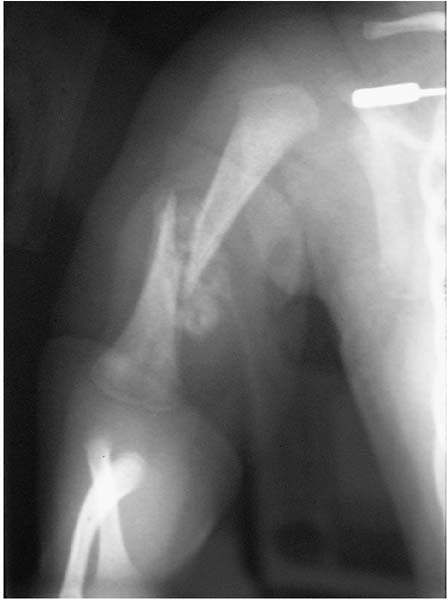

consultation in the newborn nursery is for an infant who does not move

an arm. The diagnoses that usually come quickly to mind are brachial

plexus injury or fracture. However, infection is the most important

diagnosis to make, as it can usually be treated if discovered early,

but may lead to permanent disability if the diagnosis is delayed (Fig. 10-1).

| ▪ FIGURE 10-1 A: The diagnosis of neonatal infection was delayed in this child. An AP radiograph of the humerus at 3 months of age demonstrates significant osteomyelitis and subsequent fractures. B: Approximately 1 year later there is an absence of most of the proximal humerus and severe changes of the distal humerus as well. |